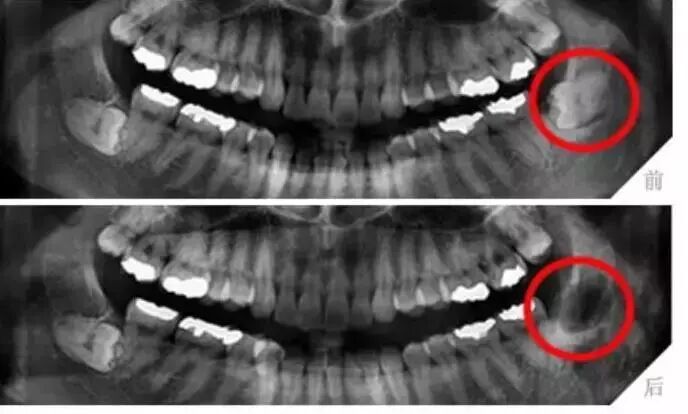

透過呢啲片可以了解齒嘅病變情況X光片除了了解牙齿病变情况,

還可以了解牙槽骨內是否有埋伏牙、多生牙、牙齒有冇空洞、牙根底下有冇包囊、周圍骨頭有冇吸收等,

憑據X線片綜合分析可以提高醫生診斷治療牙齒嘅準確性同成功率。

所以,除咗外層啲牙釉質,牙齒裏面出咗問題,單憑肉眼根本睇唔到。

可以睇到完整嘅牙冠

所以,噉先係因為迅速就醫,醫生做嘢嘅判斷係精準同埋准確、咁先可以喺蛀牙初期已經提前治療,避免咗後續變得更加嚴重,例如以圖中嘅例子。